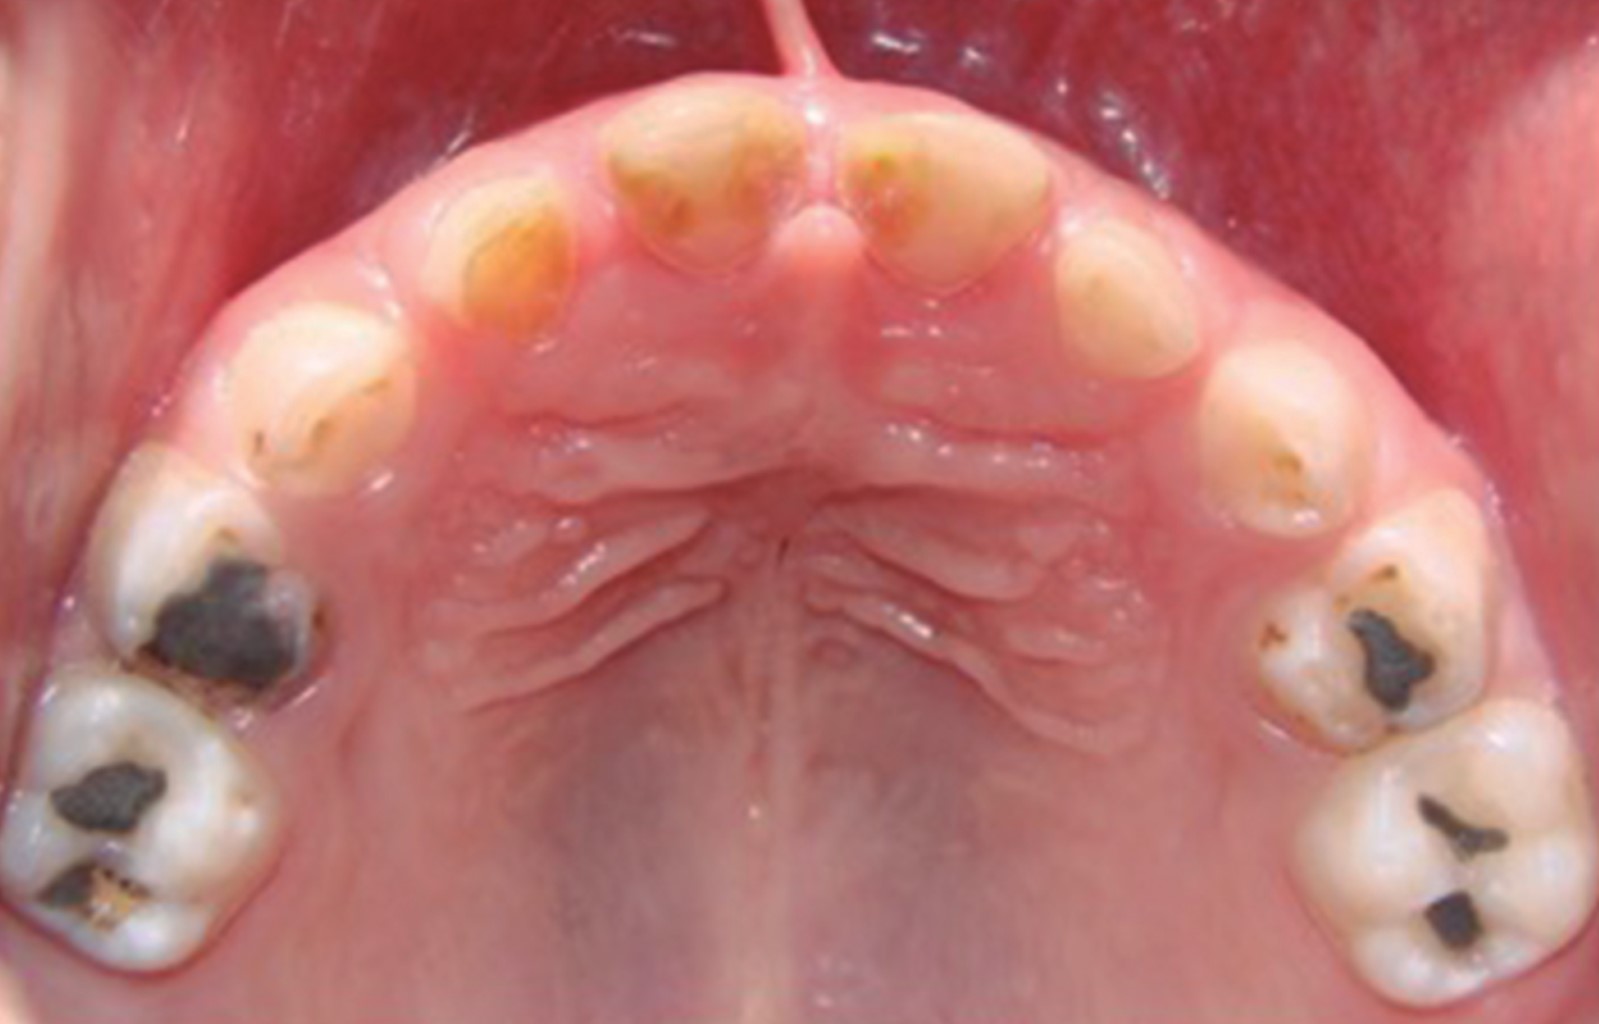

Figure 4